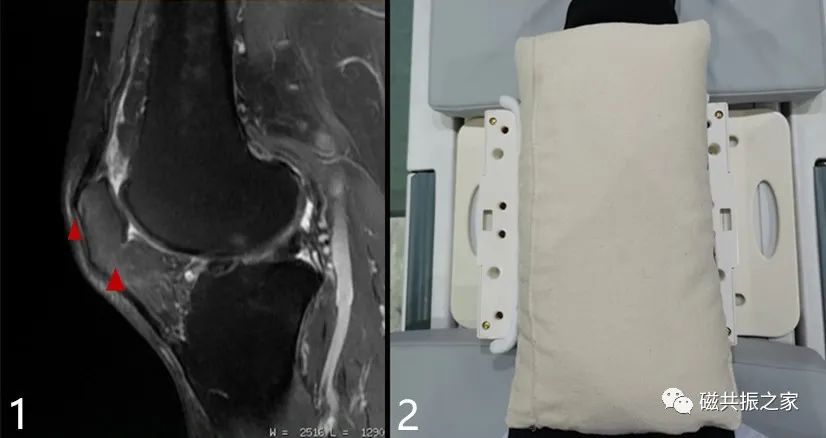

在实际扫描中会遇到部分受检者髌骨前缘或下缘脂肪垫压脂不均的情况图1△,此时可以使用沙袋适当压迫加以改善,图2△。